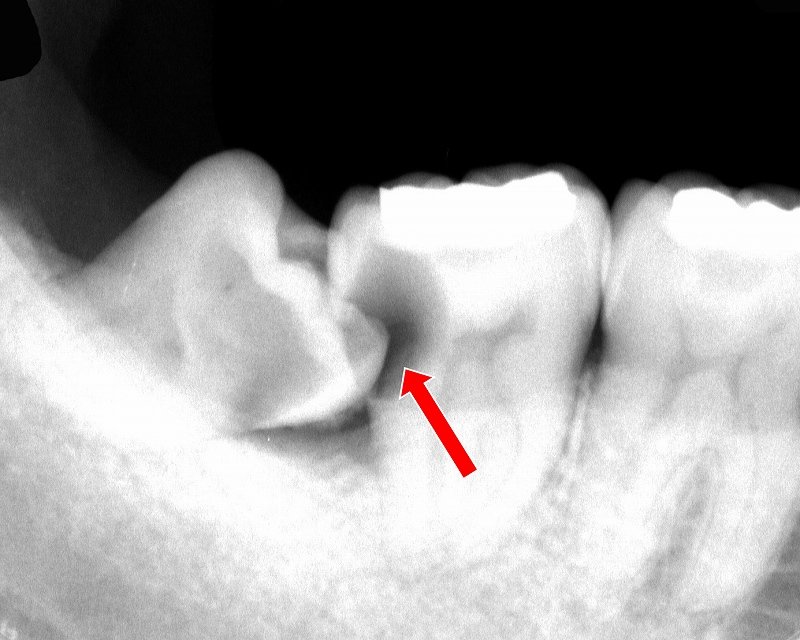

斜めや横向きに生えるリスク

親知らずは斜めや横向きに生えることが多く、隣の歯とのすき間に汚れが溜まりやすい構造です。このため、親知らず虫歯だけでなく、隣接する奥歯(二番目の大臼歯)まで虫歯が広がるリスクがあります。